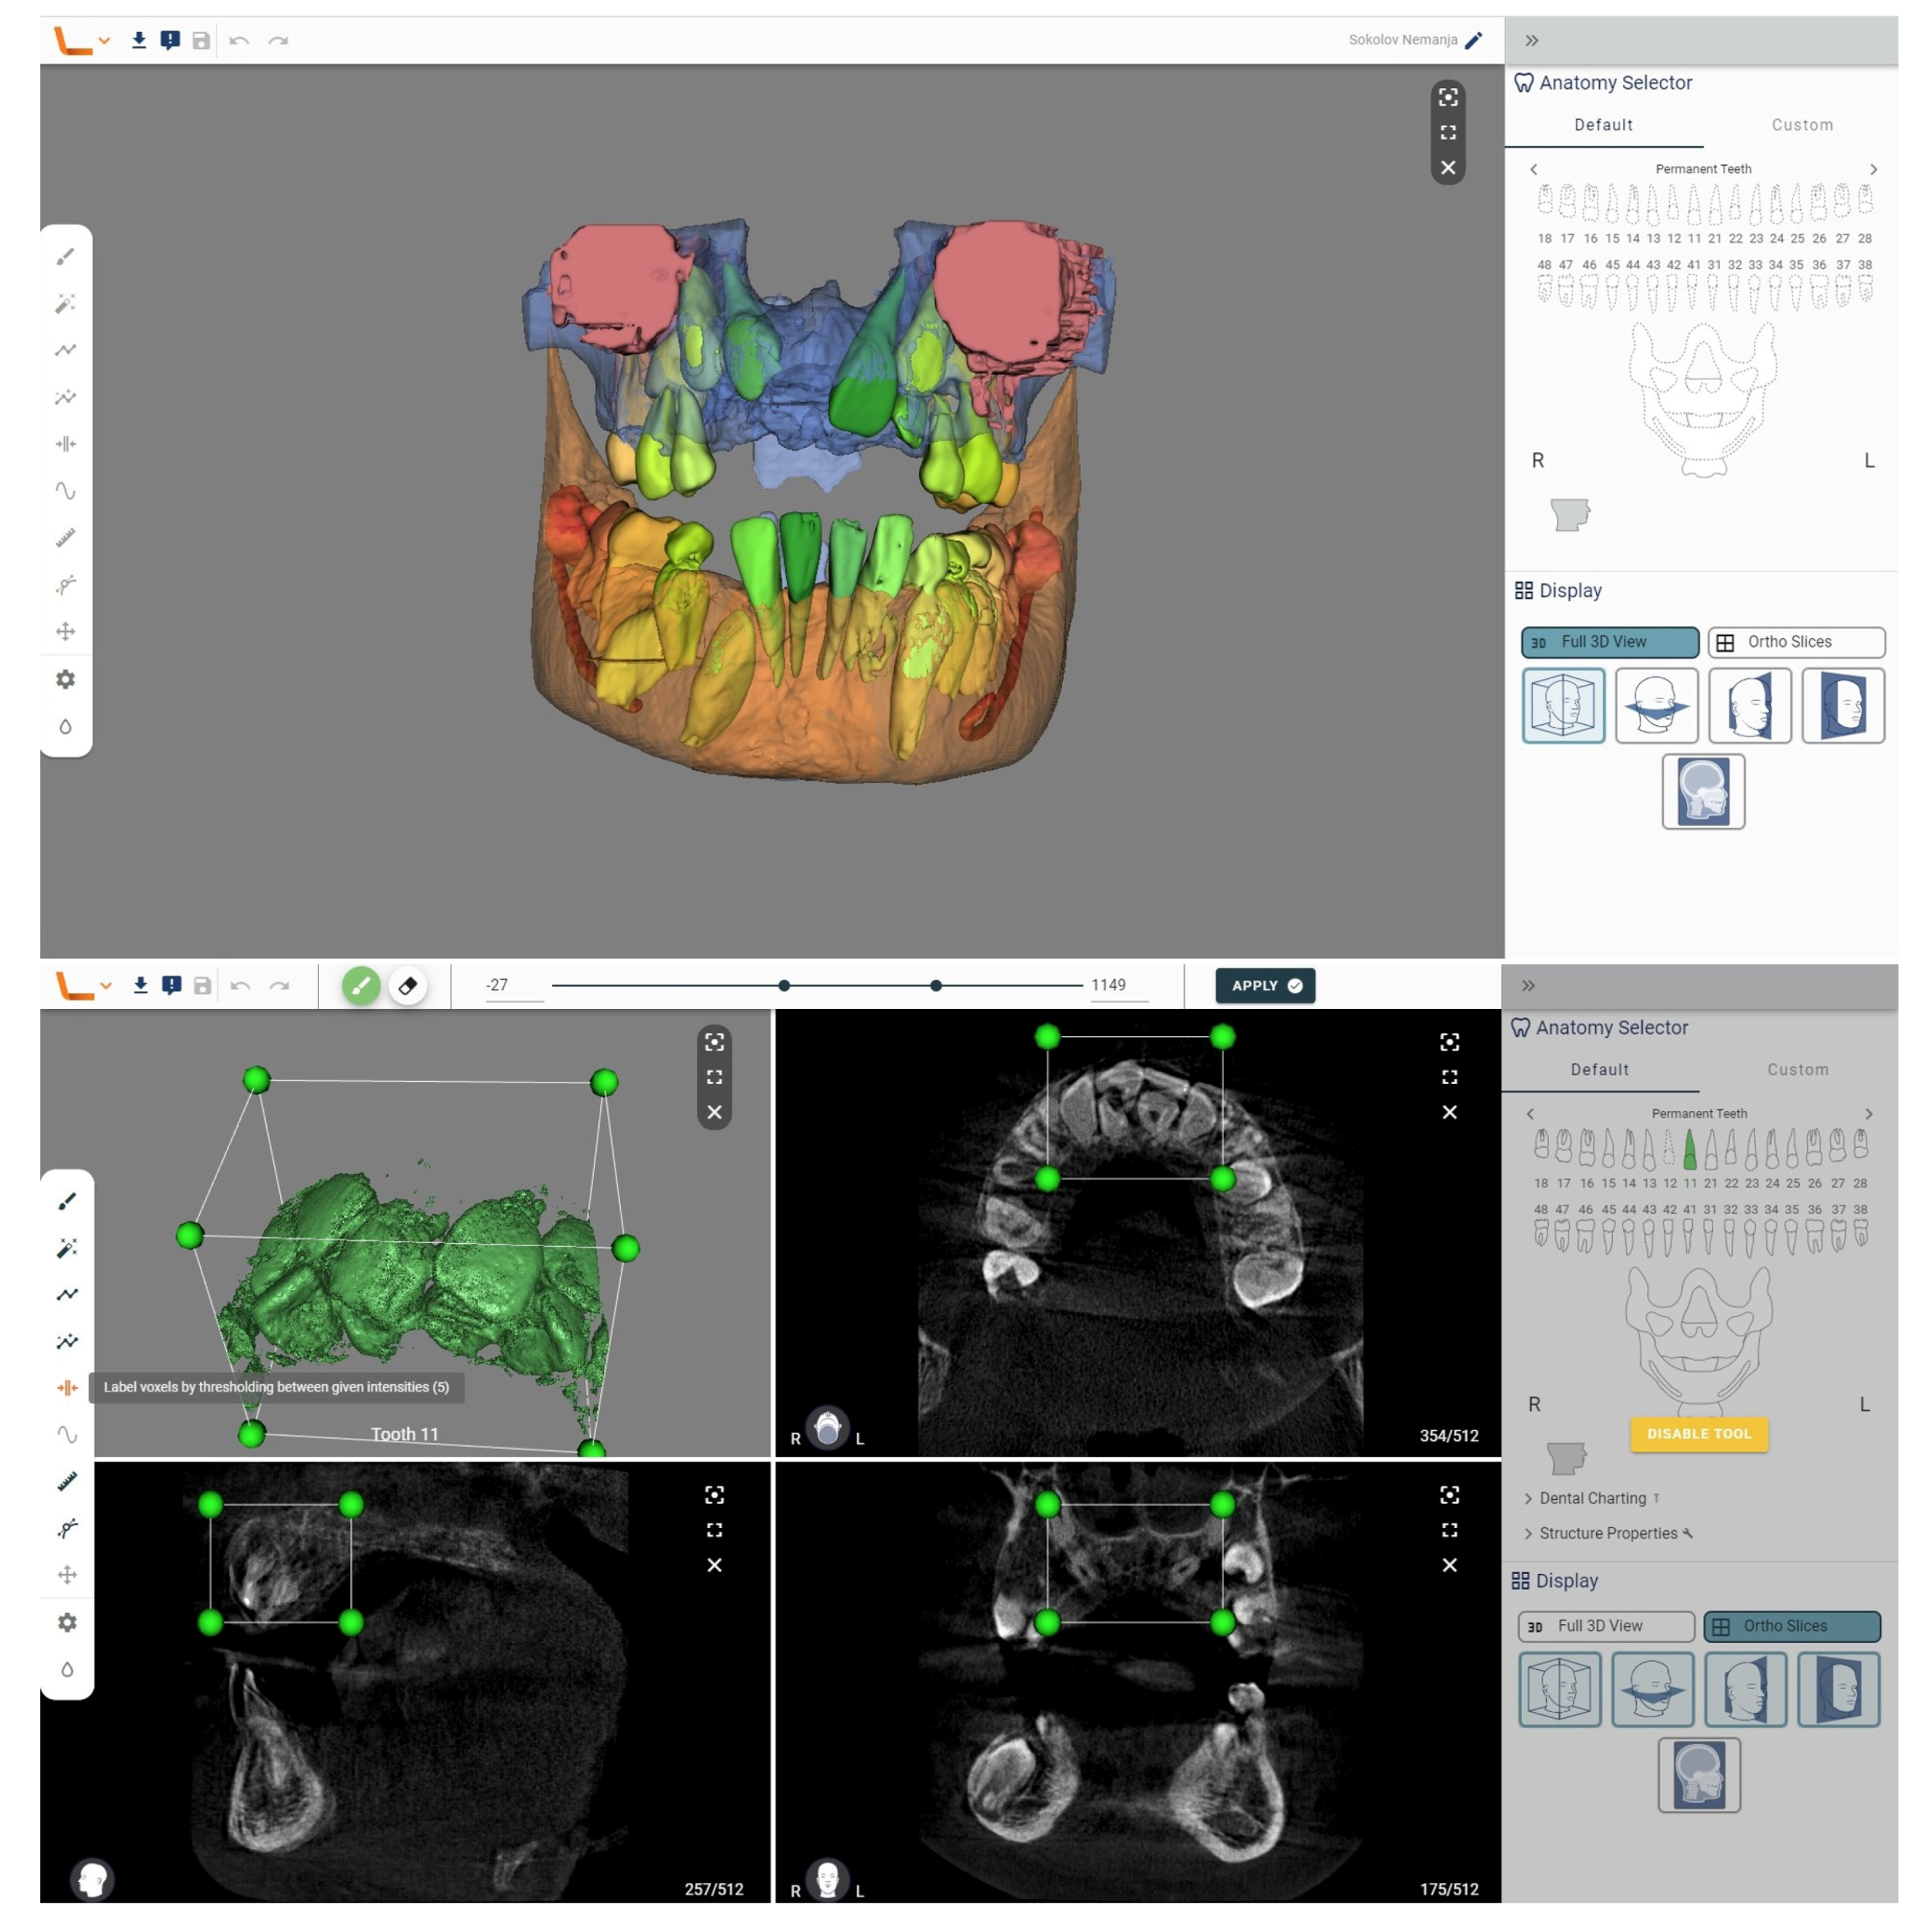

The Diagnocat Inc. (San Francisco, CA, USA) AI system exploits a set of pre-trained semantic segmentation networks based on internally modified, fully convolutional 3D U-Net architecture to obtain voxel-perfect segmentation. Image analysis takes only a few minutes (around 5 min for CBCT), and the software generates a detailed report on the condition of each tooth, along with suggestions for further diagnosis (DICOM format is required). In just a few steps, segmentation is achieved in the integrated 3D viewer. Alongside the simple selection of desired structures and teeth, this tool offers the option of STL export, which is of exceptional importance for digital dentistry. Exported 3D models can be valuable for learning as well as for creating guides for potential surgical intervention. In our case, this tool recognized all the supernumerary teeth through automatic segmentation. A mesiodens is shown, all lateral incisors are duplicated, three duplicated premolars and one distomolar are present in each jaw. Diagnocat is a fully automated tool, so it does not allow for additional settings in analysis or segmentation, only the export of the 3D model. By simply selecting the structures, a simulation of the removal of supernumerary teeth can be prepared.

Figure 2.